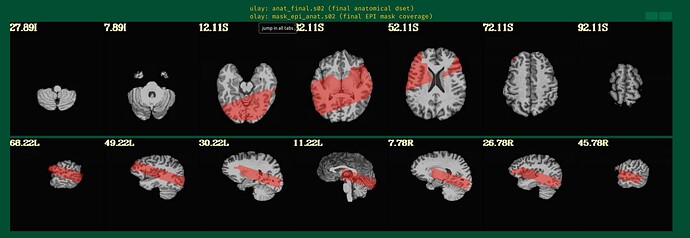

This is the beginning of output. When checking the volumes in original space, the images when applying obliquity look almost correct. That's what I acquired.

But when checking for EPI to Anat alignment, it looks like follows (almost like applying re-obliquing twice):